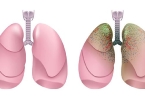

肺部点状高密度影的原因

肺部点状高密度影可能由肺炎、肺结核、尘肺、肺结节或肺钙化灶等原因引起,需结合影像学特征及临床表现综合判断。1、肺炎细菌或病毒感染可能导致肺部炎症反应,影像学表现为点状高密度影。患者常伴有咳嗽、发热、咳 ...